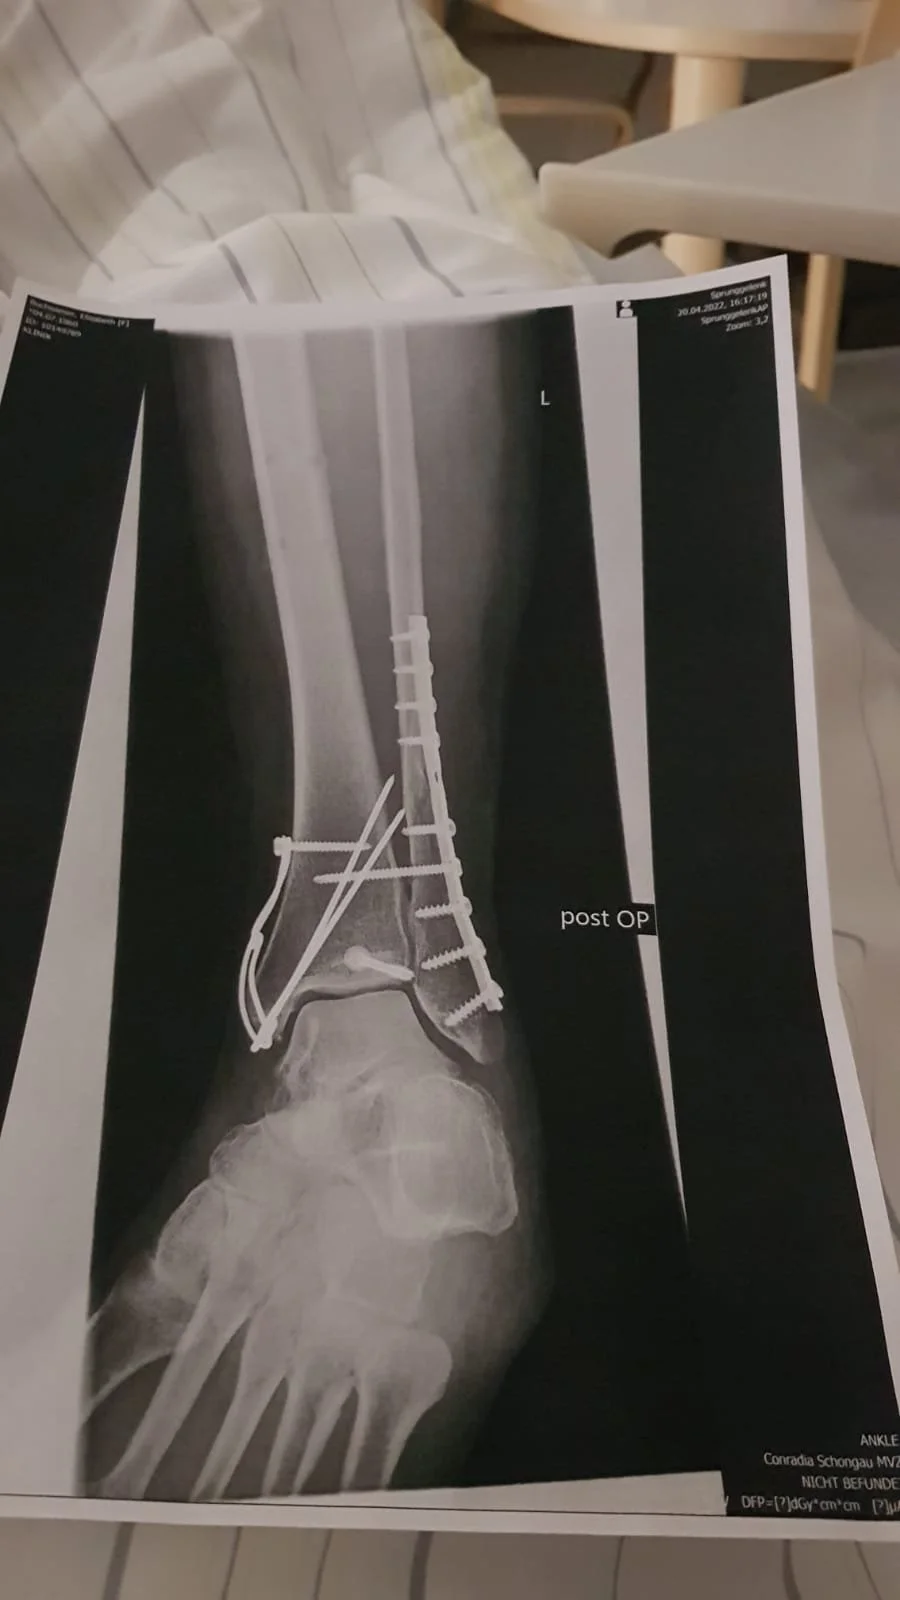

Eigentlich wollten Elisabeth und ich nur noch "schnell" im Stall abmisten bevor wir ganz gemütlich frühstücken wollten. Beim Zaun ist Elisabeth hängen geblieben und hat sich diesen Drehbruch zugezogen. Der Notarzt hat 8 min gebraucht, Eva ist gleichzeitig angekommen. Nach einer Stunde stand ich alleine da und habe versucht mich zu sortieren. Irgendwie hatten wir uns Ostern anders vorgestellt.

Jetzt war Elisabeth erst mal im Krankenhaus. OP erst nacheiner Woche. So kann sich in einer Sekunde ganz viel ändern.